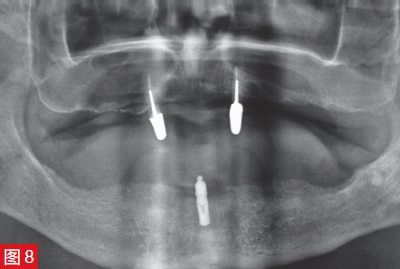

上頜骨4顆以下的成活率為69.7%,而4顆種植體的成活率顯著提高至89.1%。因此,可以推薦在下頜種植 1、2 或 4 顆種植體,從而提高成功率。對于上頜活動義齒,應計劃至少 4 顆種植體。如果將目前的數據情況與 25 年前的圖 15 中的治療方案進行比較,下頜骨和上頜骨將顯示出明顯的差異。有一種觀點認為,在下頜中,可以借助球帽附件將種植體放置在中間以保留覆蓋義齒(圖 8 和 9)。但是,對于上頜,有兩個植入物保留)當前研究不再涵蓋這種情況。上頜骨至少需要 4 個種植體,

圖 8:微創治療方案,覆蓋義齒僅由一個“中心”放置的種植體支撐。

圖 9:在中心放置的種植體上使用球形帽附件。